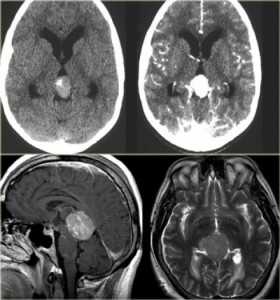

КТ и МРТ головного мозга. Аксиальные КТ до и после контрастировали, сагиттальная МРТ с контрастировавшем, аксиальная Т2-взвешенная МРТ головного мозга. Герминома (КТ и МРТ)- опухоль области шишковидной железы